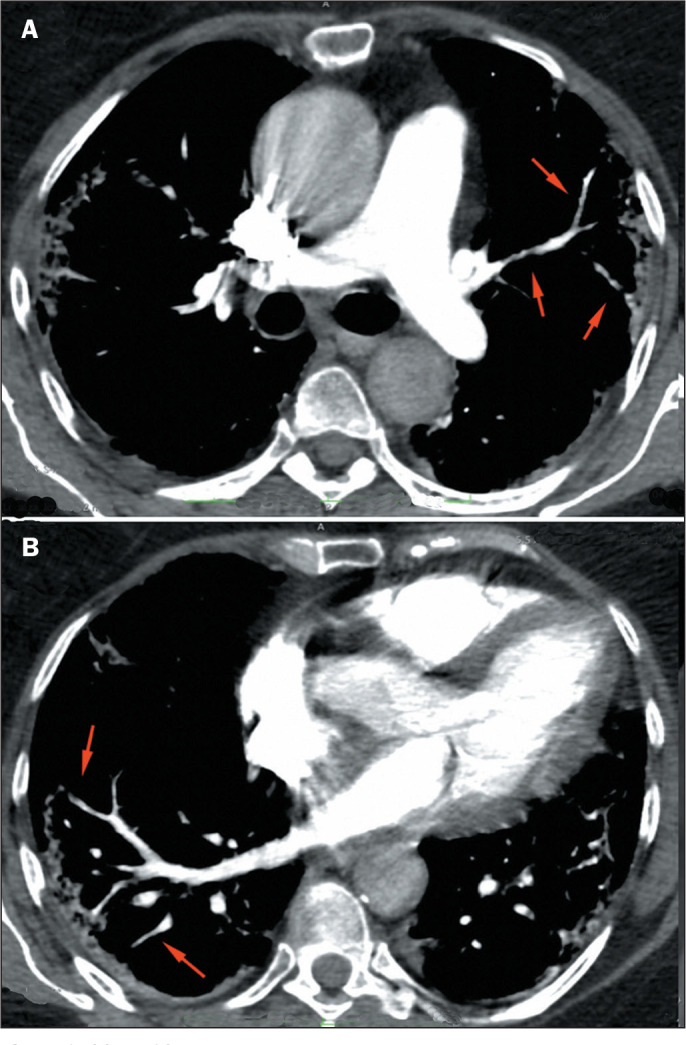

Objective: The purpose of this study was to evaluate the characteristics and meaning of the vessel wall irregularities sign, observed on computed tomography angiography of the pulmonary arteries of patients with coronavirus disease 2019 (COVID-19) pneumonia.

Results: The vessel wall irregularities sign was observed in 50 (76.9%) of the 65 patients with COVID-19. Among those 50 patients, the vascular involvement was predominantly mixed (arterial and venous) in 43 (86%), subsegmental in all 50 (100%), segmental in 13 (26%), bilateral in 46 (92%), affecting 4-5 lobes in 35 (70%), mainly in the right lower lobe in 46 (92%), and mainly in the left lower lobe in 44 (88%).

Conclusion: The vessel wall irregularities is a prevalent sign of vascular involvement in patients with COVID-19.